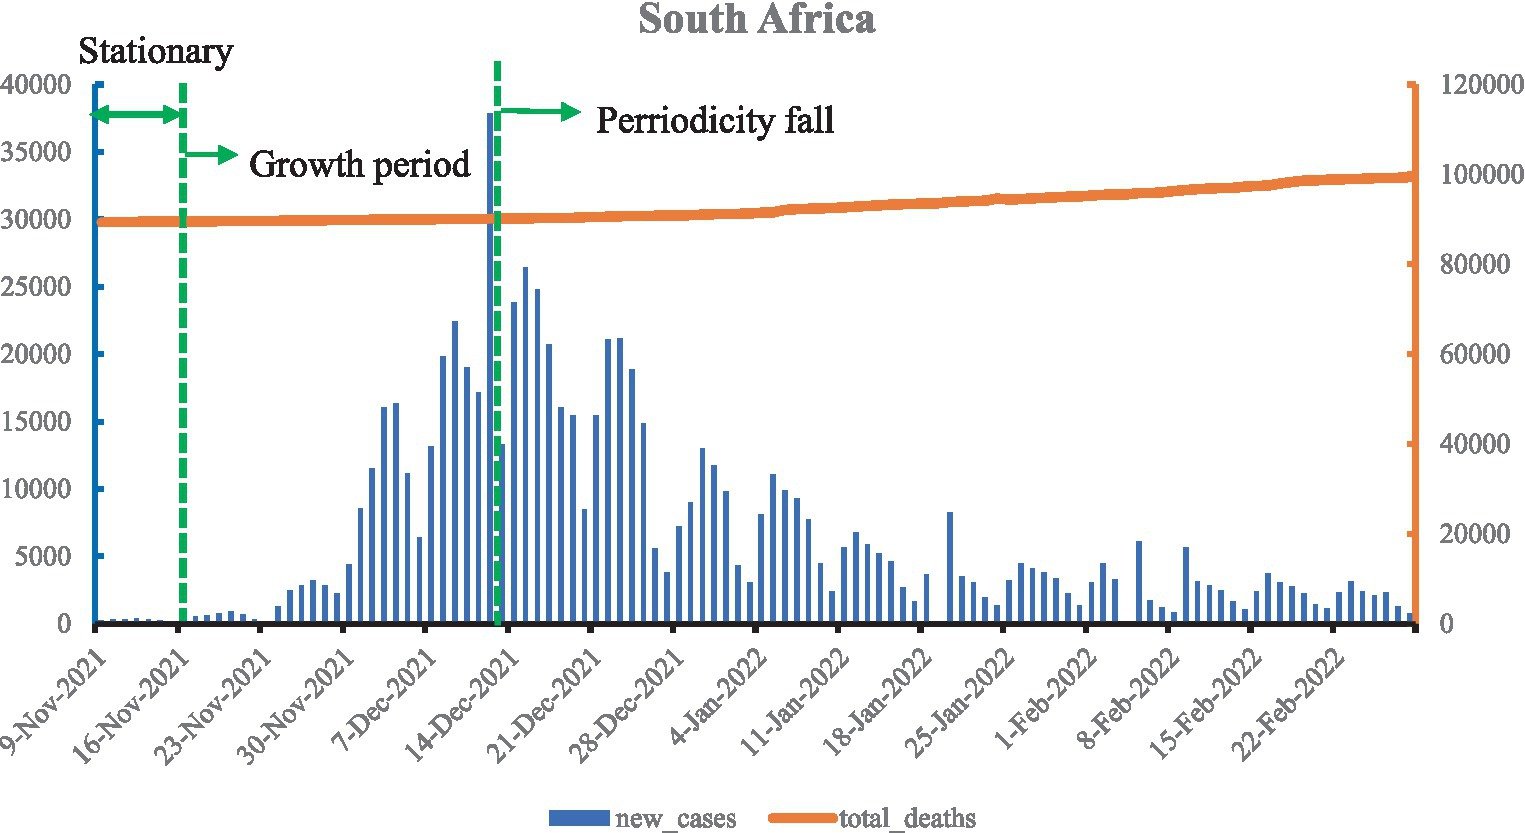

CDC: Autism Diagnoses Rise Among US Children

## CDC Report Shows Rise in Autism Diagnoses Among US Children, Sparking Debate **Atlanta, GA** –...

Autism Diagnoses Rise Among US Children

## Autism Diagnoses Rise Among US Children: Improved Detection or Cause for Concern? **Atlanta, GA*...